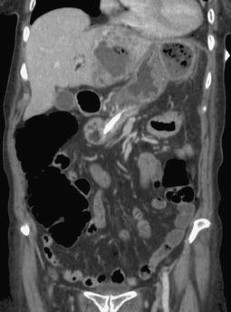

Bei einer 63-jährigen Patientin mit o. g. Risikofaktoren, einem Pancreas divisum und vermeintlichem zystischen Pankreasschwanztumor, der sich als Pseudozyste bei einer Pankreatitis herausstellte, erfolgte eine 2-jährige Behandlung rezidivierender Pankreatitisschübe. Erst bei der Behandlung eines komplizierenden Leberabszesses fiel in einer CT eine malignitätssuspekte, zum Aufstau des Pankreashauptganges führende Pankreaskopfraumforderung auf. Retrospektiv waren Gangveränderungen schon auf Voraufnahmen sichtbar. Die partielle Duodenopankreatektomie bestätigte das Pankreaskopfkarzinom.

A 63-year-old female patient with suspected cystadenocarcinoma of the pancreas tail, which was resolved as a pancreatic pseudocyst, was treated for recurrent pancreatitis for 2 years. A tumor in the pancreas head was only detected on a follow-up CT after resection of a complicating liver abscess. In retrospect, progressive pancreatic duct anomalies were visible on previous scans. Partial duodenopancreatectomy confirmed the presence of a pancreas head carcinoma.